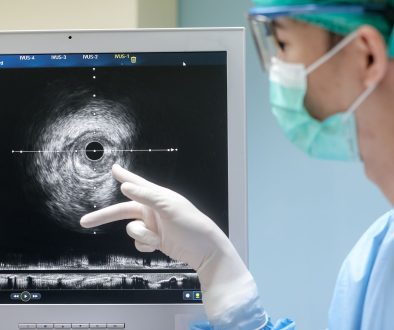

ما الذي يحدث أثناء الجراحة؟

الجراحة تختلف بناءً على نوع الورم وموقعه. تهدف العملية إلى إزالة أكبر قدر ممكن من الورم مع الحفاظ على الوظائف الحيوية للدماغ. يقدم الجراحون توقعات واضحة حول ما يمكن تحقيقه. التقنيات الحديثة مثل الجراحة المجسمة وجراحة الأعصاب بمساعدة الكمبيوتر قد تحسن من نتائج الجراحة.